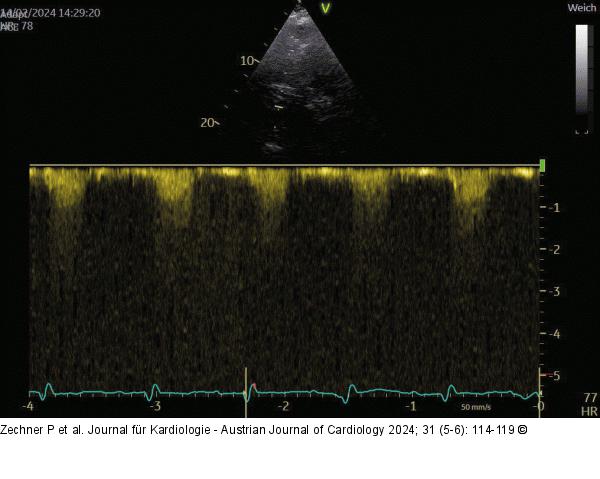

Abbildung 5: Echo AS ohne KM: kein CW-Spektrum bei sehr schlechten Schallbedingungen |

Abbildung 5: Echo

AS ohne KM: kein CW-Spektrum bei sehr schlechten Schallbedingungen |